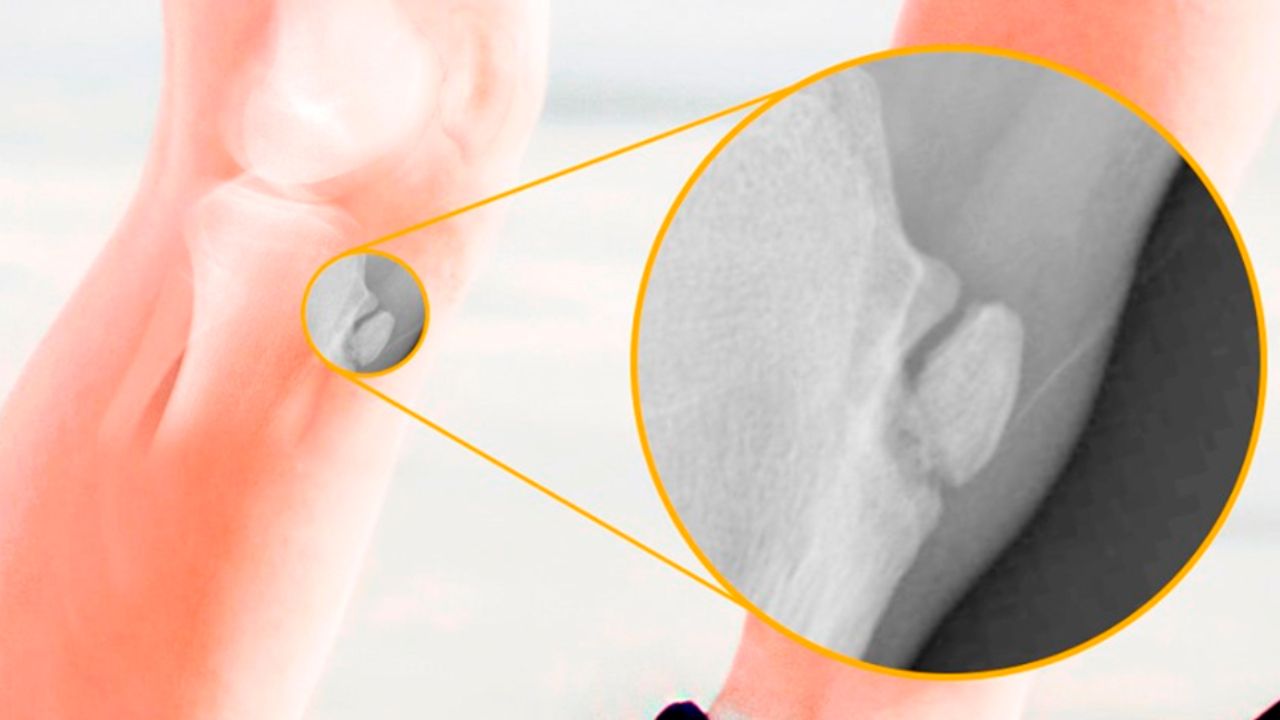

O diagnóstico é simples e realizado pelo ortopedista através do exame físico e da história clínica do paciente. O raio-x pode ser solicitado para descartar outras patologias, como fraturas ou tumores ósseos, e geralmente mostra a irregularidade ou fragmentação na tuberosidade da tíbia característica da síndrome. É importante tranquilizar os pais e o paciente de que se trata de uma condição autolimitada, ou seja, que tende a se resolver sozinha conforme o esqueleto amadurece.

O tratamento visa o controle da dor e a manutenção das atividades na medida do possível. Aplicação de gelo após os exercícios e uso de analgésicos são recomendados para as crises de dor. A fisioterapia é muito importante e foca no alongamento da cadeia posterior e do quadríceps para diminuir a tração sobre o tendão, além do fortalecimento muscular. Em casos de dor muito intensa, pode ser necessário reduzir temporariamente a carga de treinos, mas raramente é preciso parar o esporte totalmente. A cirurgia é extremamente rara e só considerada em adultos com sequelas dolorosas (ossículos soltos) que não melhoraram com o tempo.